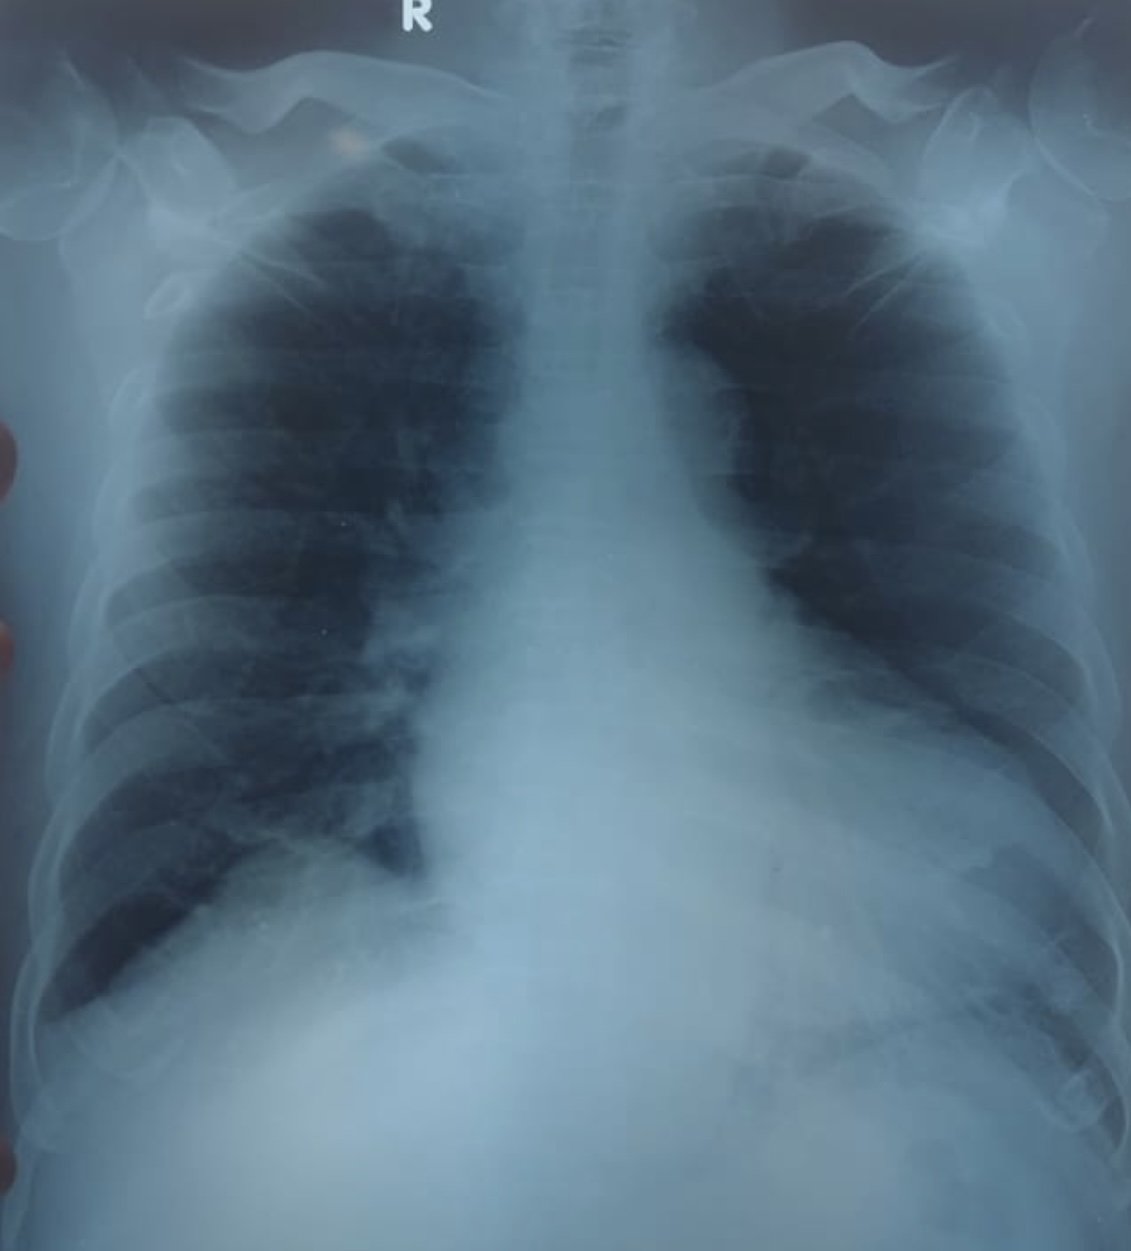

Relevant Test Results Prior to Catheterization

Chest X-ray revealed cardiomegaly with no sign of pulmonary oedema. Other laboratory results were within normal limits, except for a high-sensitivity troponin-I level of 221 ng/mL. The patient was diagnosed with a non–ST-segment elevation myocardial infarction (NSTEMI), and early percutaneous coronary intervention (PCI) was planned.